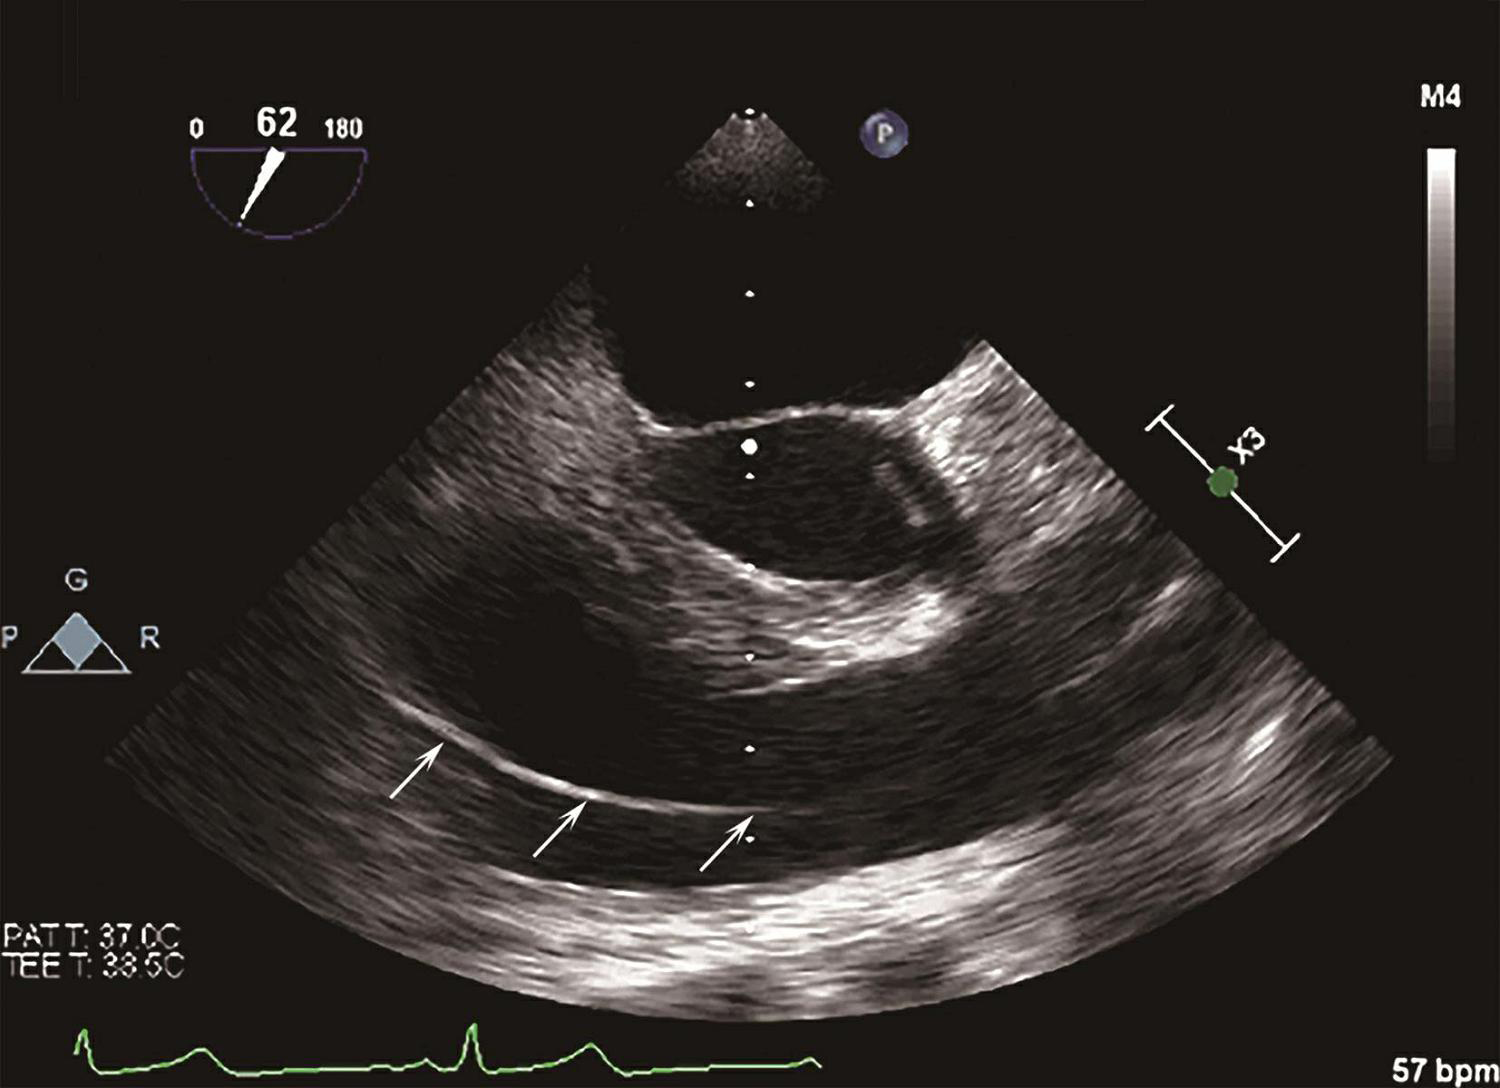

4.如果置入困难,或患者存在复杂心内畸形,如大房间隔缺损、大室间隔缺损、单心室、右心室双出口等,可以通过经胸心脏超声或经食管心脏超声辅助提高成功率(图3-1-5)。

图3-1-5 肺动脉漂浮导管食管超声影像

白色箭头示经右心室向肺动脉走行的肺动脉导管。